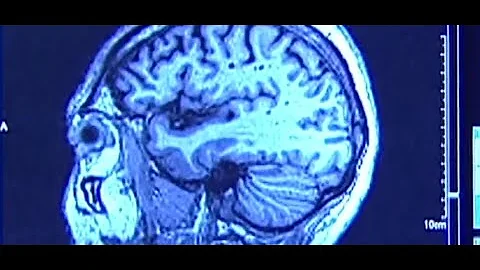

Cte Explained In 2 Minutes: The Science Behind Chronic Traumatic Encephalopathy

Boston University is at the forefront of groundbreaking research on Chronic Traumatic Encephalopathy (CTE), a progressive ...